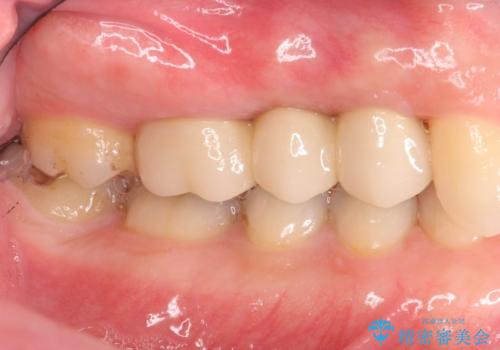

抜歯を行い、咬合機能の回復を行いますが、咬合関係や非常に強い噛み合わせの問題をふまえ、咬合面をメタルにしたメタルボンドブリッジで治療を行うこととしました。

また噛み合わせが深くブリッジの強度が十分に確保できないことから、抜歯時に歯周外科を行うことで十分に安定したクラウン装着をできるような処置を行っています。

術前・術後でブリッジ治療をした部分の歯肉ラインを整えたことで安定したブリッジを製作することができました。